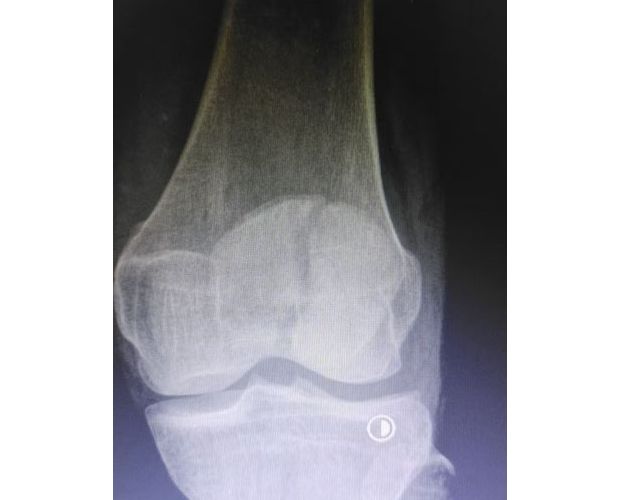

该患者因意外外伤导致髌骨骨折后,紧急前往何店镇中心卫生院就诊。该院外科医护团队迅速响应、规范处置,第一时间为患者完善各项术前检查,全面细致评估患者身体状况及骨折伤情,精准把握手术指征。为最大限度保障手术安全与治疗效果,切实减少患者往返城区医院的奔波之苦,降低就医成本,该院立即启动医共体专家协作机制,正式向曾都区人民医院申请专家技术支持。接到申请后,徐三军主任快速响应、主动下沉,带着丰富的临床经验和精湛的手术技术赶赴卫生院,与该院外科医护团队深入研讨,结合患者具体病情制定个性化手术方案,细致梳理术前各项准备工作,为手术顺利开展筑牢坚实基础。

手术现场,徐三军主任凭借多年积累的临床经验和娴熟的手术技巧,精准完成骨折复位、钢板内固定、伤口缝合等一系列关键操作,动作规范流畅、精准高效,最大限度减少手术创伤。该院外科医护团队全程密切配合、协同发力,严格按照手术规范操作,全程严密监测患者心率、血压等生命体征,及时应对术中各类突发情况,全力保障手术安全。此次手术全程顺利,术中出血量少,患者生命体征始终平稳,术后患者顺利安返病房,为后续康复治疗奠定了坚实基础。